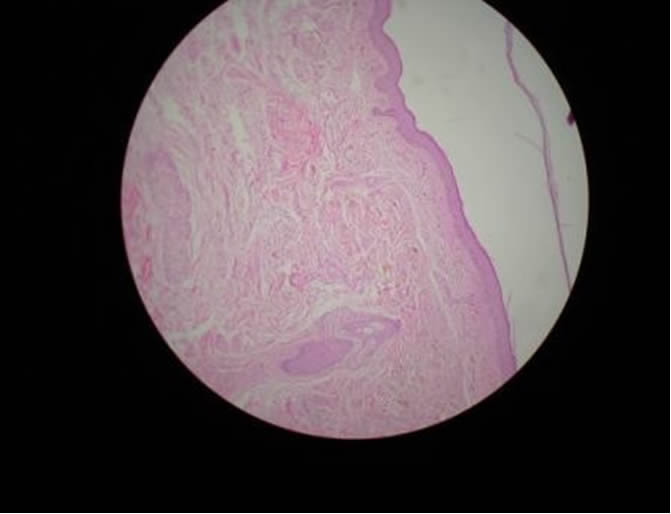

OCRONOSIS EXOGENA

OCRONOSIS - HISTOPATOLOGIA - DR. PIQUERO

OCRONOSIS y SIRINGOMAS